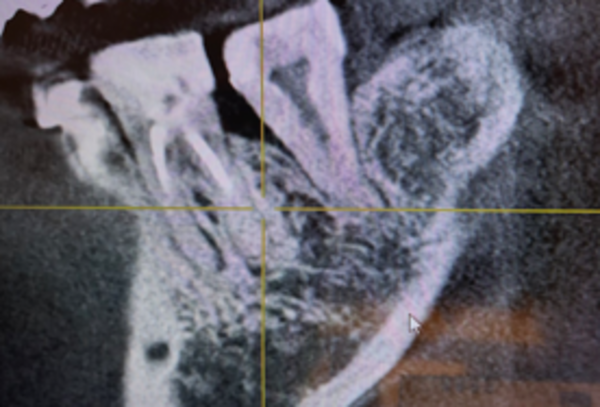

さらに詳細を確認するためにCT撮影を行ったところ、左下の一番奥歯とその手前の歯の間の骨が部分的に溶けていました。

噛み合っている上の歯には、10年以上前に他院で埋入されたインプラントが装着されていました。

インプラントは骨と強固に固定されていますので、噛む力が強くかかると、ご自身の歯の周りに炎症が起こり、骨が溶けることがあります。

今回その影響による可能性が高いと考えられました。